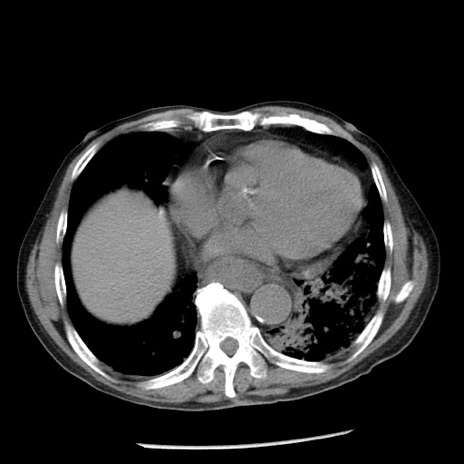

症例26(横断像)

【症例】80歳代男性

【主訴】嘔吐

【現病歴】昨晩2回嘔吐あり、今朝になっても嘔吐あり。来院。

【既往歴】胃潰瘍

【身体所見】意識清明、BT 37.6℃、BP 166/95mmHg、HR 100bpm、SpO2 97%、腹部:平坦・軟、腸蠕動音聴取良好、圧痛なし。

【データ】WBC 21900、CRP 1.46